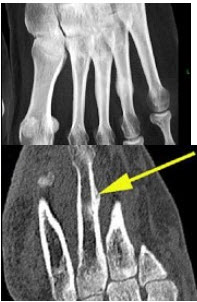

71、单项选择题

该病例临床上有持续性足部疼痛,结合图像,最可能的诊断为()

A.骨样骨瘤

B.疲劳骨折

C.尤文氏瘤

D.正常结构

E.骨软骨瘤

点击查看答案